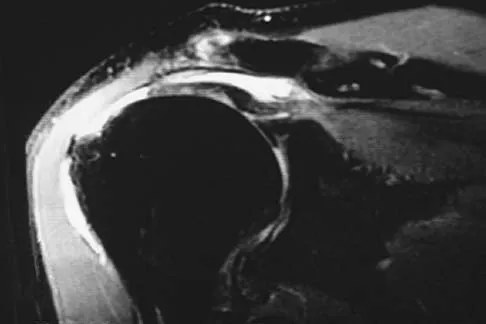

The MRI scan of the shoulder shown in Figure 2 was performed with the arm in abduction and external rotation. The image reveals what condition?

Internal impingement of the shoulder is now a well-recognized cause of shoulder pain in the throwing athlete. First described by Walch and associates, it involves contact of the rotator cuff and labrum in the maximally externally rotated and abducted shoulder, such as in the late cocking phase of the throwing motion. Schickendantz and associates have shown this contact to be physiologic in most patients and becoming pathologic with repetitive overhead activity. Schickendantz MS, Ho CP, Keppler L, Shaw BD: MR imaging of the thrower's shoulder: Internal impingement, latissimus dorsi/subscapularis strains, and related injuries. Magn Reson Imaging Clin N Am 1999;7:39-49. Walch G, Boileau P, Noel E, et al: Impingement of the deep surface of the supraspinatus tendon on the posterosuperior glenoid rim: An arthroscopic study. J Shoulder Elbow Surg 1992;1:238-245.